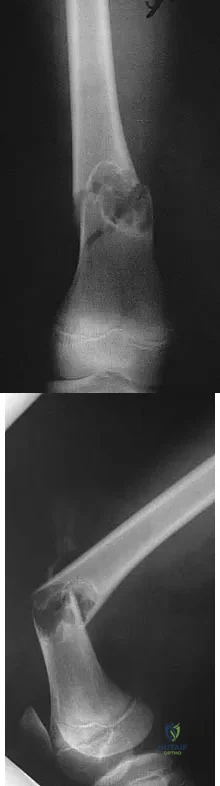

Question 8

A 30-year-old man has pain in the left arm after a motor vehicle accident. His neurovascular examination is intact, and radiographs are shown in Figures 25a and 25b. What is the best course of management?

Explanation